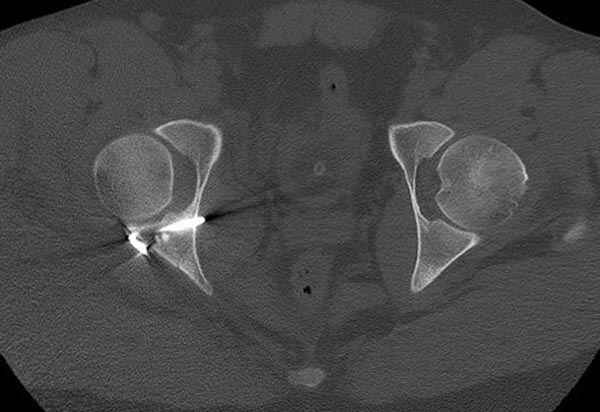

11:50 больной в послеоперационной, рентгенограмма N7, компьютерная томограмма в тот же день N8-10

Интраоперционные N5 косая запирательная и N6 подвздошный снимок